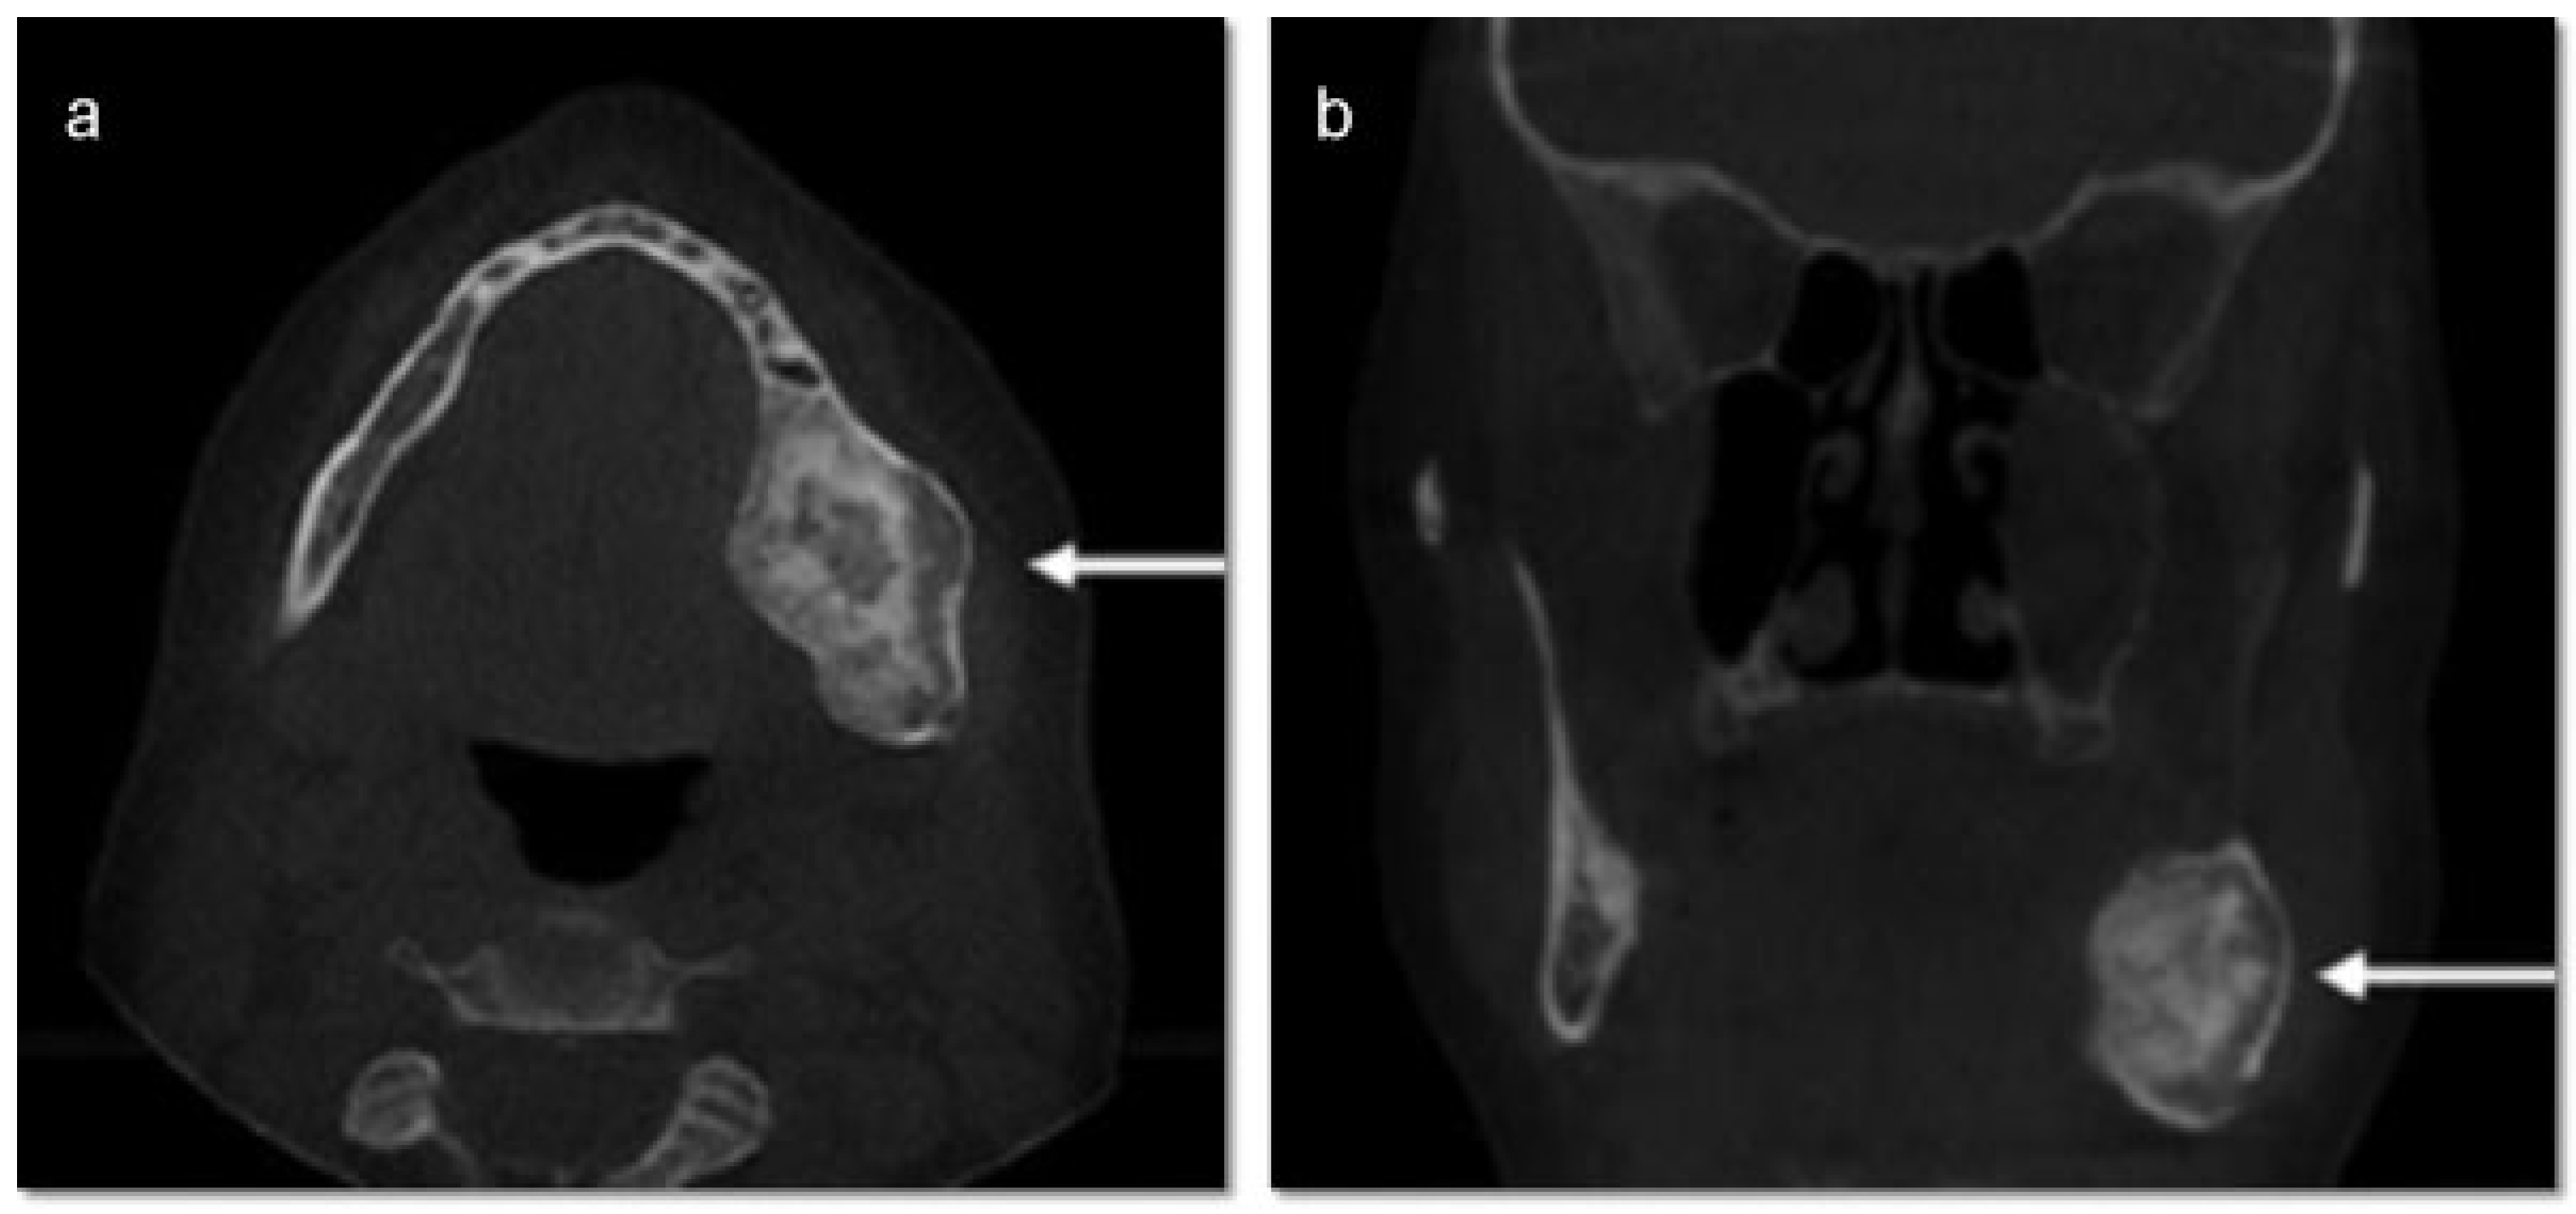

A 46-year-old Caucasian female presented to the Oral Surgery Department at Alameda County Medical Center–Highland General Hospital, complaining of dental pain in maxillary left region for 2 months. Her medical history was significant for hypertension and congestive heart insufficiency for which she takes enalapril, carvedilol, furosemide, and Klor-Con (Klor- Con®, Upsher-Smith Laboratories, Inc., Morristown, NJ) (potassium chloride). She is allergic to codeine. She has a 10 pack- year history of smoking and a remote history of methamphetamine use. Her past surgical history is significant for parathyroid carcinoma, which resulted in primary HTP. She reported that time weight loss, hives, insomnia, fatigue, and bone pain before surgical excision performed 17 years ago. No uterine or kidney lesions were present. She also reported that her brother had a jaw tumor, not surgically treated, because the “jaw growth stopped.” Unfortunately, her brother does not live in the city, and a better investigation concerning his disease could not be performed. Extraoral examination revealed a small swelling in the left mandibular border. Intraorally, the patient presented with poor hygiene with multiple extensive dental caries and periodontal disease. An asymptomatic and firm posterior left mandibular swelling was also present, with buccal and lingual expansion. Radiographic and computed tomography (CT) scan examination revealed a 5-cm mixed radiolucent and radiopaque image in the left mandibular body with well-defined borders and base expansion (Figure 1 and Figure 2a,b). An incisional biopsy was obtained with an intraoral approach which was diagnosed as a benign fibro-osseous lesion, consistent with ossifying fibroma. Initial laboratory analysis prior surgery showed a small increase in serum calcium of 10.5 mg/dL (8.4–10.2 mg/dL). Based on these findings and with the history of parathyroid carcinoma, the patient was referred to an endocrinologist. CT scan of the neck was unequivocal for recurrence and no correction of serum calcium was necessary. The association of ossifying fibroma with primary HPT due parathyroid carcinoma, with a family history of a similar jaw lesion, led to a high suspicion of HPT-JT syndrome. It was extensively discussed with the patient, but she refused to perform any genetic test. Our treatment planning initially included the extraction of the left inferior premolars, which had extensive caries lesions and mobility, performed before the lesion surgical removal. It would enable a better wound closure after resection. Three months later (2010 March), the ossifying fibroma was surgically resected with 5 mm margins (Figure 3) using an intraoral approach, and a 2.4-mm reconstruction plate was placed from the left mandibular ramus to the parasymphysis (Figure 4a–c). The postoperative course was remarkable only for neurosensory disturbance in the left inferior alveolar nerve, which improved but was not completely resolved after 3 years of follow-up. Seven months later (2010 October), using an extraoral approach, the patient underwent a left mandibular reconstruction using her left posterior iliac crest, as well as the right anterior iliac crest. The corticocancellous blocks were secured with 2.4 mm monocortical screws, while cancellous bone chips were inserted between the block grafts (Figure 5a–c). Although regular follow-ups were performed within the first 4 postoperative months, the patient recently returned to the oral surgery clinic for revaluation in 2012. Clinical and radiological examinations (Figure 6) were performed, and oral rehabilitation with dental implants was planned (June 2012). The patient subsequently underwent a third surgical intervention, under local anesthetic and intravenous sedation. The remaining maxillary teeth were extracted, followed by osteoplasty and placement of four implants: two anterior axially placed and two posterior tilted placed. At the same operating time, monocortical screws were from the mandible and three implants were placed in the region of teeth 20, 21, and 28, and alloplastic bone graft was placed covering the exposed threads of the implants (Figure 7a,b). A temporary superior and inferior prostheses were subsequently placed, and a period of 6 months for implant osseointegration before final prosthesis rehabilitation is being observed. The patient is currently followed regularly and, after 3 years of surgical resection, no evidenceof tumor recurrence is seen (Figure 8). Therefore, no evidence of parathyroid carcinoma recurrence is seen after 21 years of endocrinological follow-up.

Figure 2. (a) Axial CT scan showing the mixed radiolucent and radiopaque image in the left body mandibular. (b) Coronal CT scan showing the mixed radiolucent and radiopaque image in the left body mandibular. CT, computed tomography.